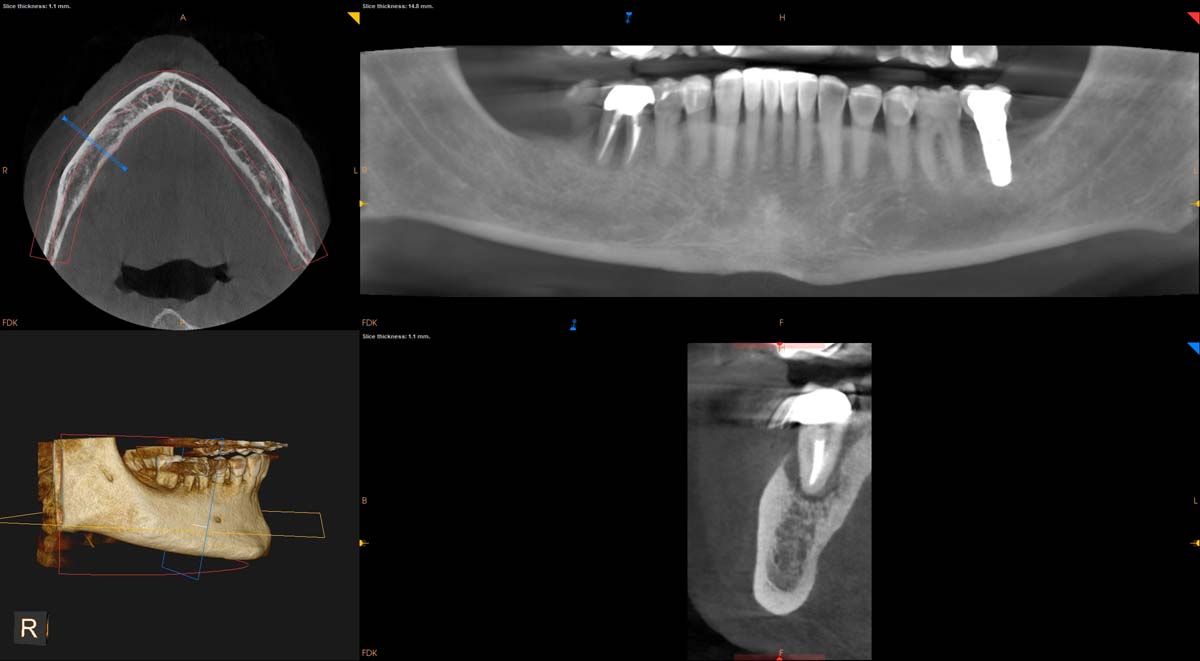

Tip: Use CBCT to Educate Patients to Make Informed Treatment Decisions

We used to try showing patients their clinical situation on 2D x-rays and demonstrating treatment using models. Later, digital intraoral cameras helped, but they could not show much more than what a patient could see in a mirror. Today, it is possible to show patients every angle of their clinical situation in hyperrealistic 3D with a CBCT scan. Now, when I recommend treatment to patients and they ask why, I am armed with an interactive image captured by my CS 8200 3D extraoral imaging system (Carestream Dental). I scroll through the tooth and bone, point out lesions below the surface, and show why there is or is not enough bone for an implant. If you use something like the Prosthetic-Driven Implant Planning module to automatically merge an intraoral scanner file with the CBCT scan, you create an even more accurate picture. How much easier is it for the patient to accept treatment when they are seeing the end results of that treatment?

The CBCT revealed the extent and solidified the opportunity to make the correct clinical decision